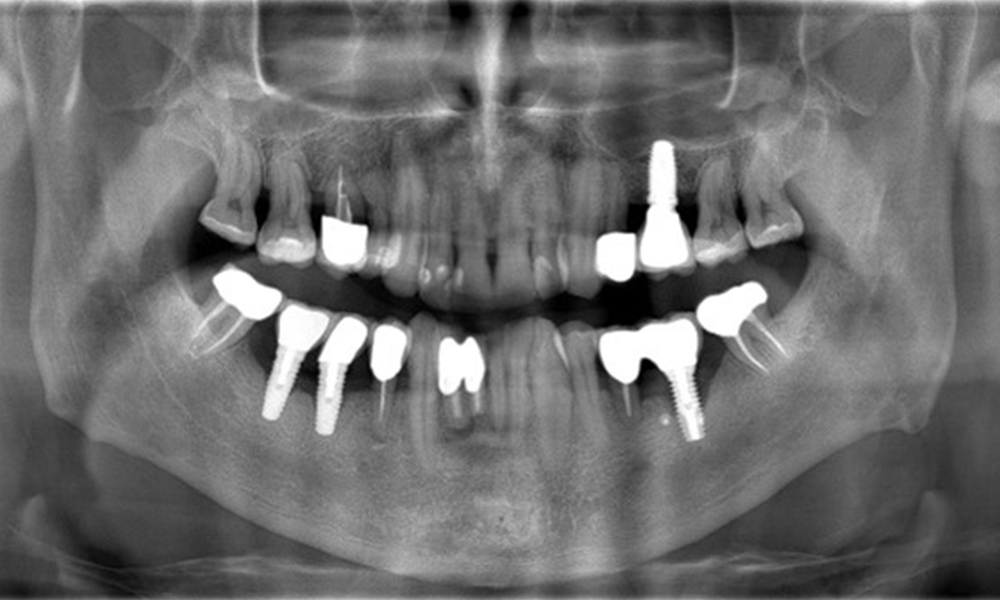

A 52-year-old patient presents at a preventive care session. The patient has no systemic disease and is not taking any medication. He has had various dental treatments and also has two active carious lesions. In addition, the patient has four implants (2nd, 3rd and 4th quadrants). He is revealed to have early periodontal disease (stage IV, grade B). His periodontal condition is stable; a probing depth of Probing depths (ST) of 5 mm is only evident at the implant in region 36. Gingivitis is also identified.

The X-ray images show the progression of bone loss.

The X-ray images show the progression of bone loss. OPG from 29.06.2020 (left) and OPG from 26.02.2024 (right).

The X-ray images show the progression of bone loss in the area of the implant in region 36: dental film from 11.02.2021 (left) and dental film from 18.01.2024 (right).